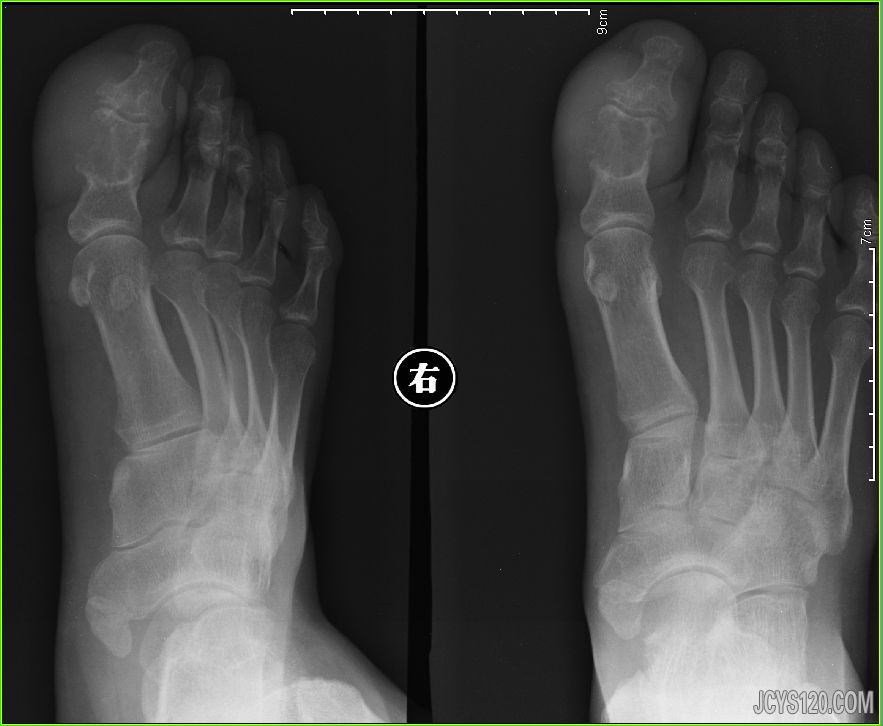

男,40岁,足趾肿大,偶有疼痛数月,近几日加重。 检查可见拇趾周围软组织肿大,密度增高,骨组织密度减低,边缘清晰。 阅读全文>